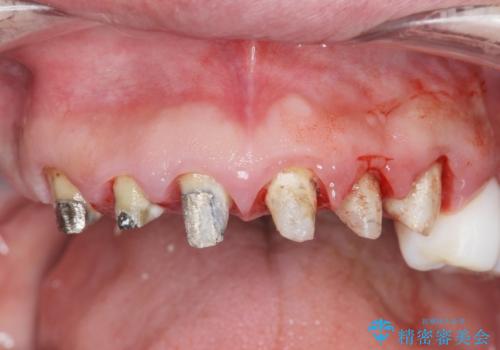

[ 歯周外科手術 ] セラミック治療後の歯ぐきの違和感

- 「セラミック治療を他院で受けたが、それ以来歯ぐきが腫れ違和感がある、改善してほしい。」と歯ぐきの状態改善を希望され来院されました。

歯周組織検査を行うと歯ぐきからは容易に出血し、X線検査より歯とセラミッククラウンの適合が悪い(ピッタリと合っていない)状態が示唆され、歯ぐきの炎症を惹起している状態でした。

セラミッククラウンを除去し仮歯を装着し、歯周外科手術を行い歯ぐきの状態を改善したのち、適合の良いセラミッククラウンを再作製をする治療計画としました。